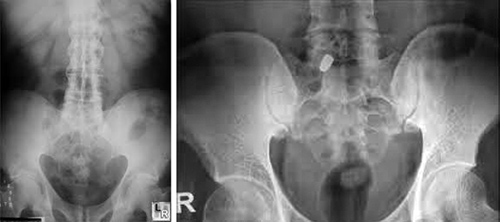

Οσφυαλγία λόγω ιερολαγονίτιδος

Η ιερολαγονίτις, όπως λέει και η ονομασία είναι ένα είδος φλεγμονής (όλα τα εις «-τις» είναι φλεγμονές, π.χ. αμυγδαλίτις) που αφορά την μία ή και τις δύο αρθρώσεις τις λεκάνης προς την σπονδυλική στήλη. Δηλαδή της άρθρωσης που συνδέει το ιερό οστούν με τα δύο λαγόνια.

Φλεγμονή πραγματική της ιερολαγονίου είναι σπανιότατη. Αυτό που συμβαίνει είναι ένας ερεθισμός σε πολύτοκες γυναίκες, της μίας από τις δύο αρθρώσεις. Το πιο σημαντικό είναι όταν πάσχουν οι αρθρώσεις στις περιπτώσεις αγκυλοποιητικής σπονδυλίτιδος, οπότε οι αρθρώσεις κλείνουν (παύουν να είναι αρθρώσεις).

Επίσης σε περιπτώσεις καταγμάτων της λεκάνης μπορεί η ιερολαγόνιος να εμφανίσει εξάρθρημα (ή υπεξάρθρημα).